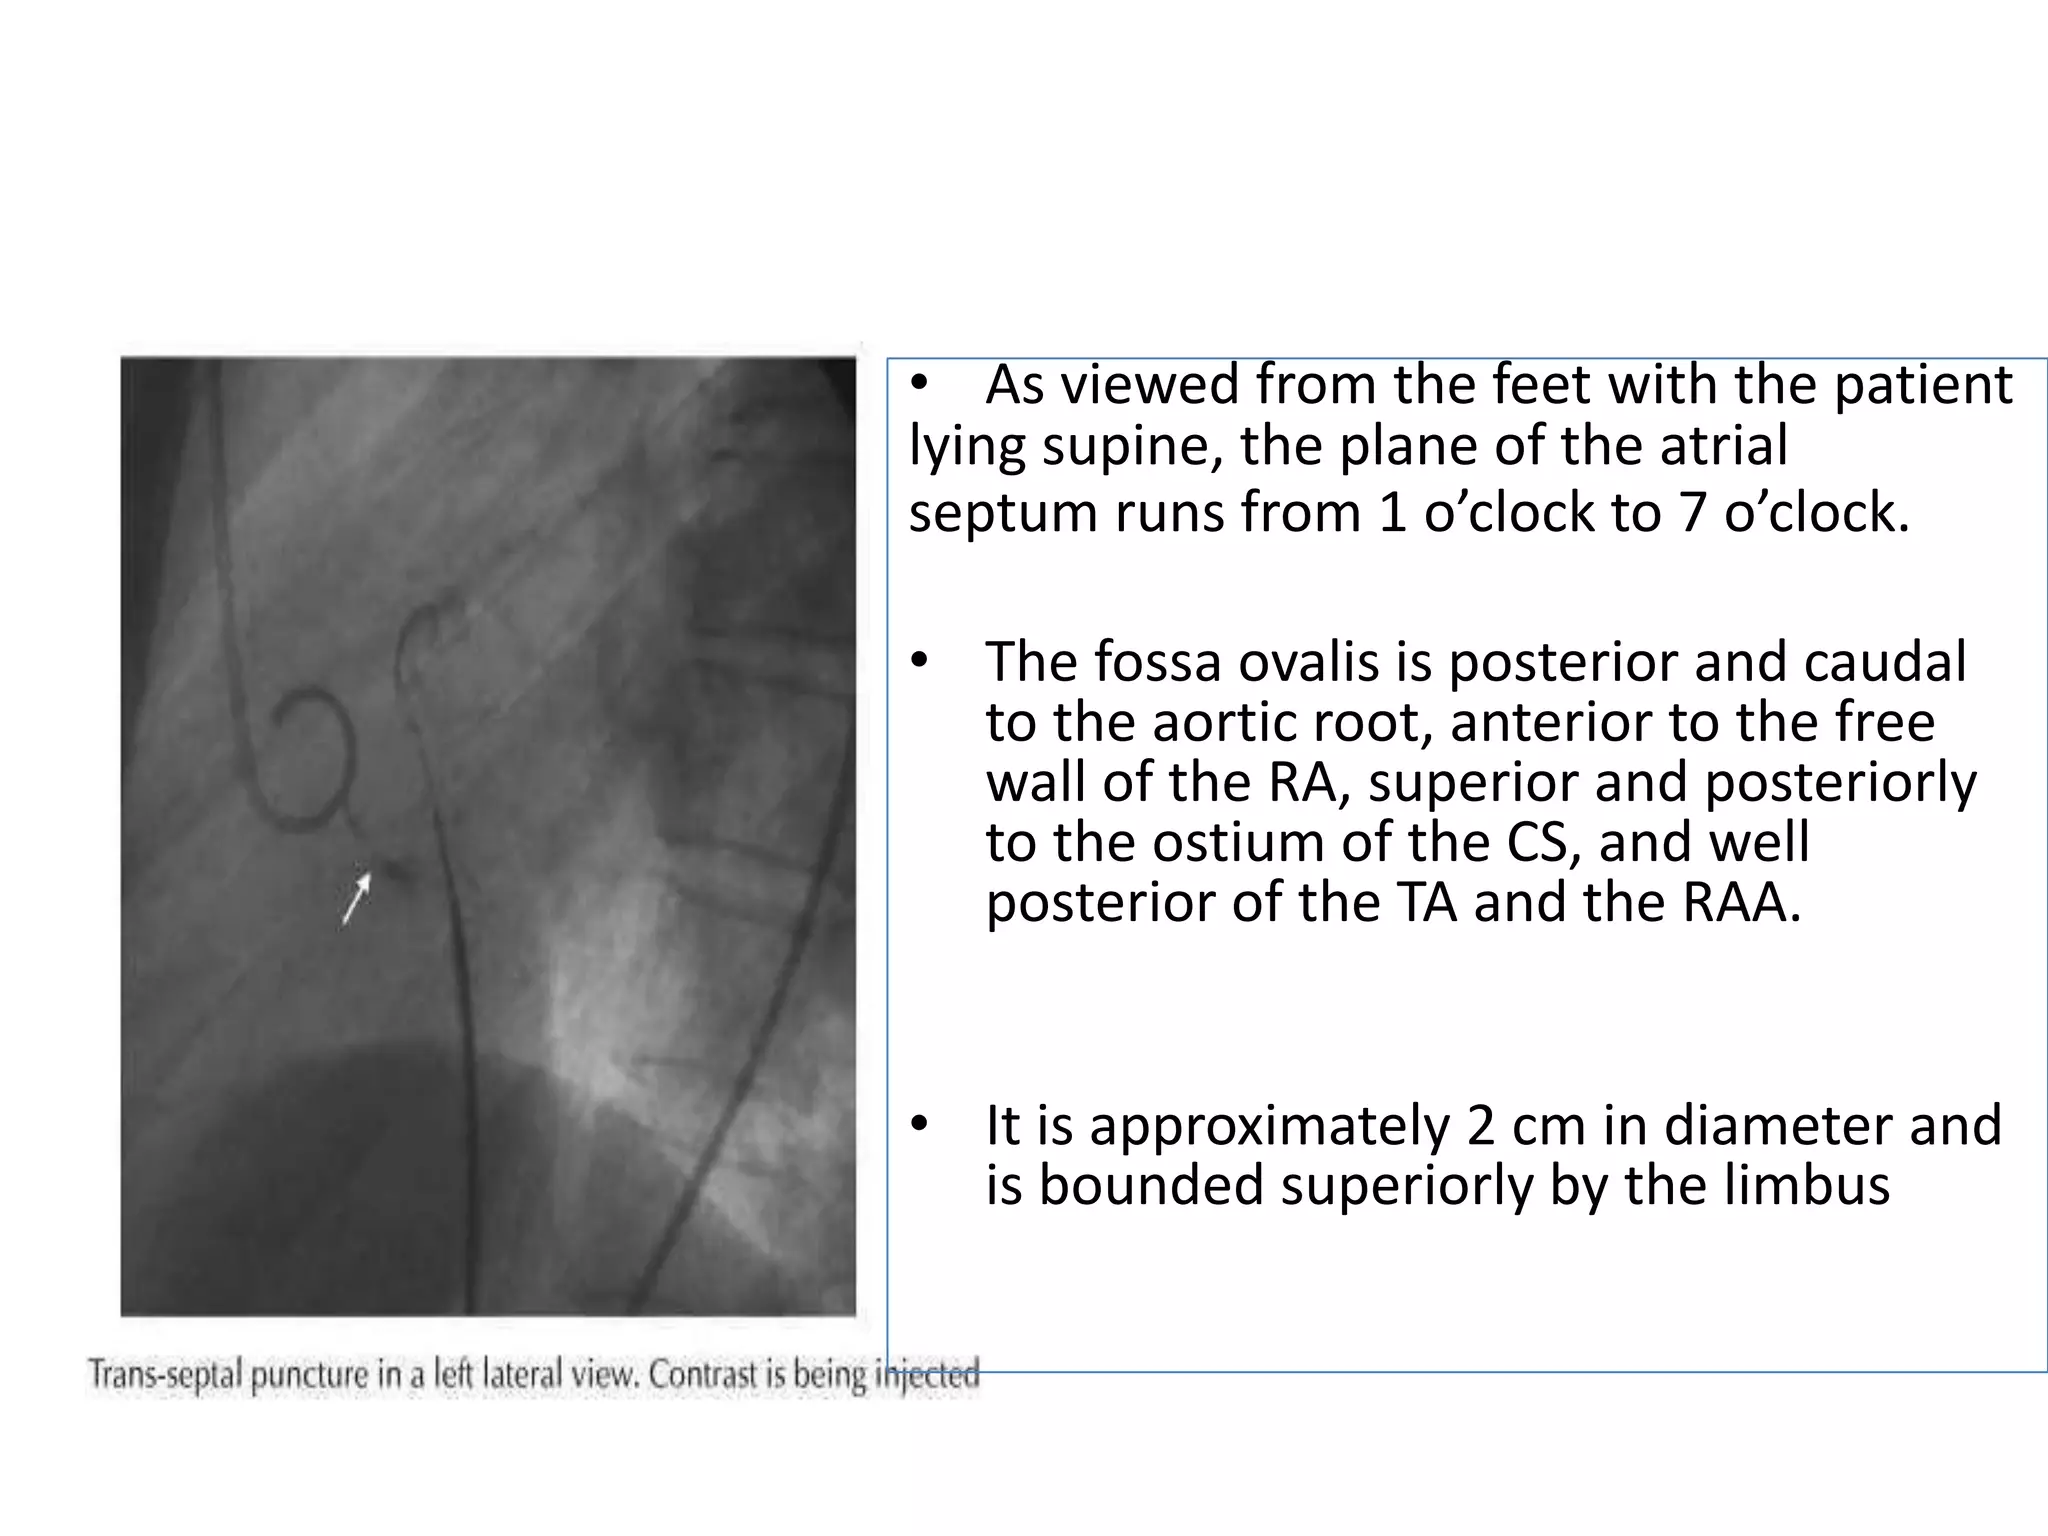

• As viewed from the feet with the patient

lying supine, the plane of the atrial

septum runs from 1 o’clock to 7 o’clock.

• The fossa ovalis is posterior and caudal

to the aortic root, anterior to the free

wall of the RA, superior and posteriorly

to the ostium of the CS, and well

posterior of the TA and the RAA.

• It is approximately 2 cm in diameter and

is bounded superiorly by the limbus